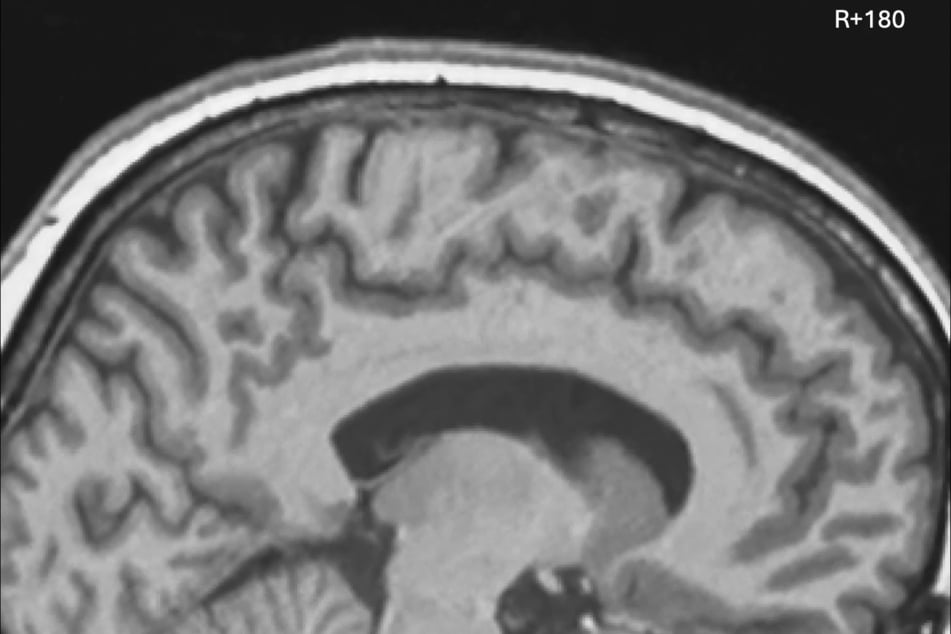

Los meses en el espacio cambian a las personas: los astronautas de larga duración muestran desplazamientos cerebrales notables.

Los meses en el espacio cambian a las personas: los astronautas de larga duración muestran desplazamientos cerebrales notables.  © PNAS/Brain displacement and nonlinear deformation following human spaceflight

El hallazgo: tras la estancia en el espacio, el cerebro se sitúa más arriba y más atrás dentro del cráneo que en la Tierra. Los cambios afectan principalmente las áreas responsables del equilibrio, la orientación y el movimiento.

Los cambios fueron especialmente notorios en los astronautas que pasaron seis meses o incluso un año completo en la Estación Espacial Internacional.